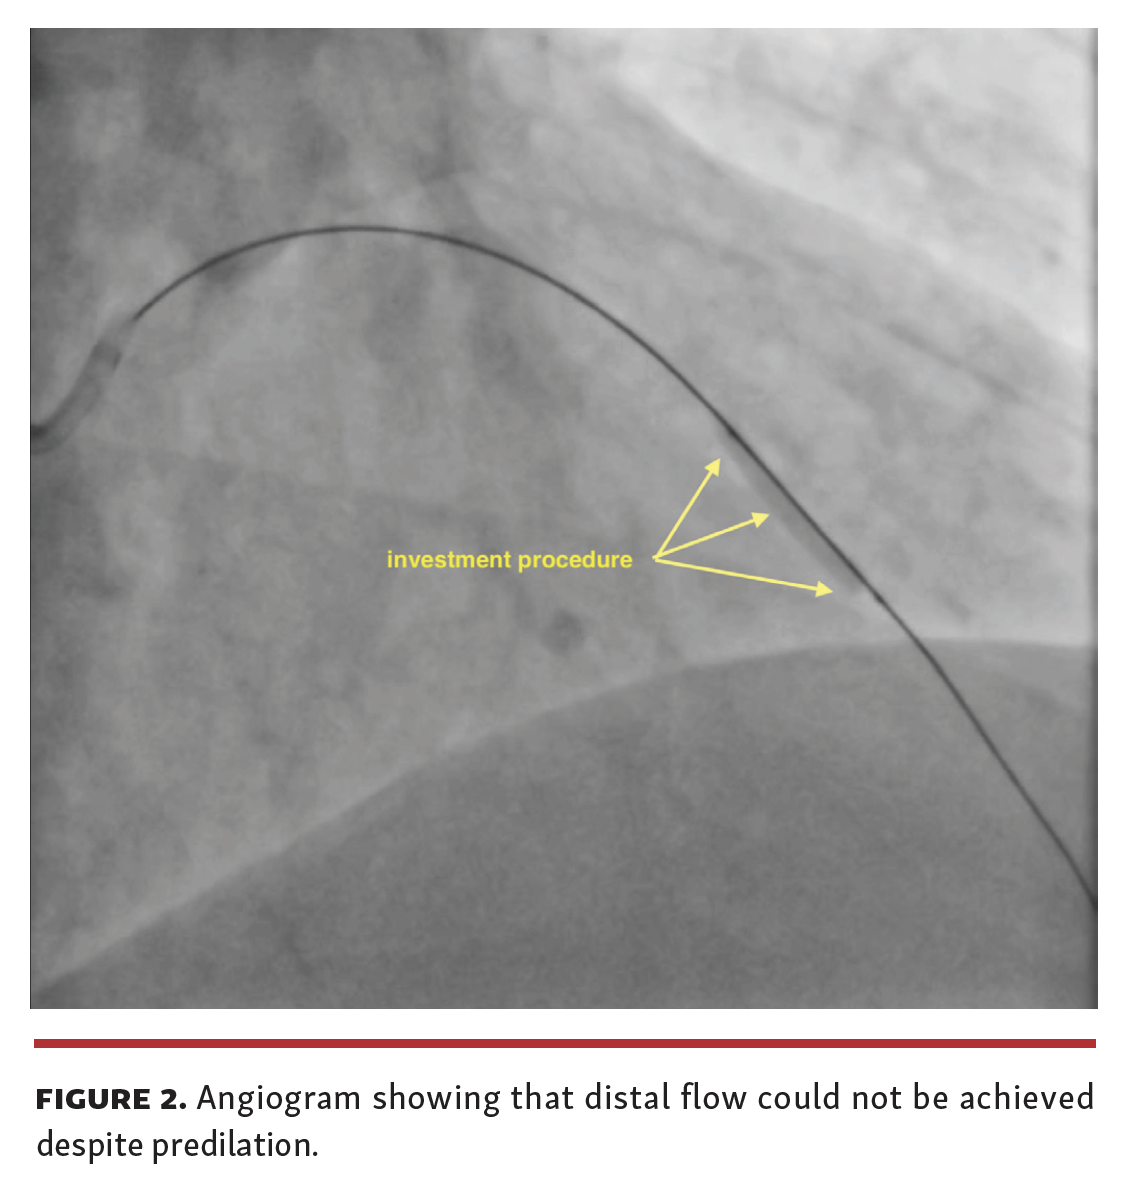

A 48-year-old male patient with a known diagnosis of hypertension presented after 6 months of chest pain (Canadian Cardiovascular Society II-III). Coronary angiography (CAG) showed a chronic total occlusion (CTO) of the left anterior descending (LAD) coronary artery from the mid-region (Figure 1 and Video Series). Percutaneous coronary intervention (PCI) was planned upon detection of viable tissue with myocardial perfusion scintigraphy. The distal portion of the CTO lesion was passed with microcatheter support and a hydrophilic wire. Distal flow could not be achieved despite successive predilations with small-diameter balloons (Figure 2). It was decided to implement an investment procedure to facilitate the next PCI process. Control angiogram 6 months later showed Thrombolysis in Myocardial Infarction (TIMI) 3 flow in the distal lumen of the LAD and there was no residual stenosis (Figure 3).